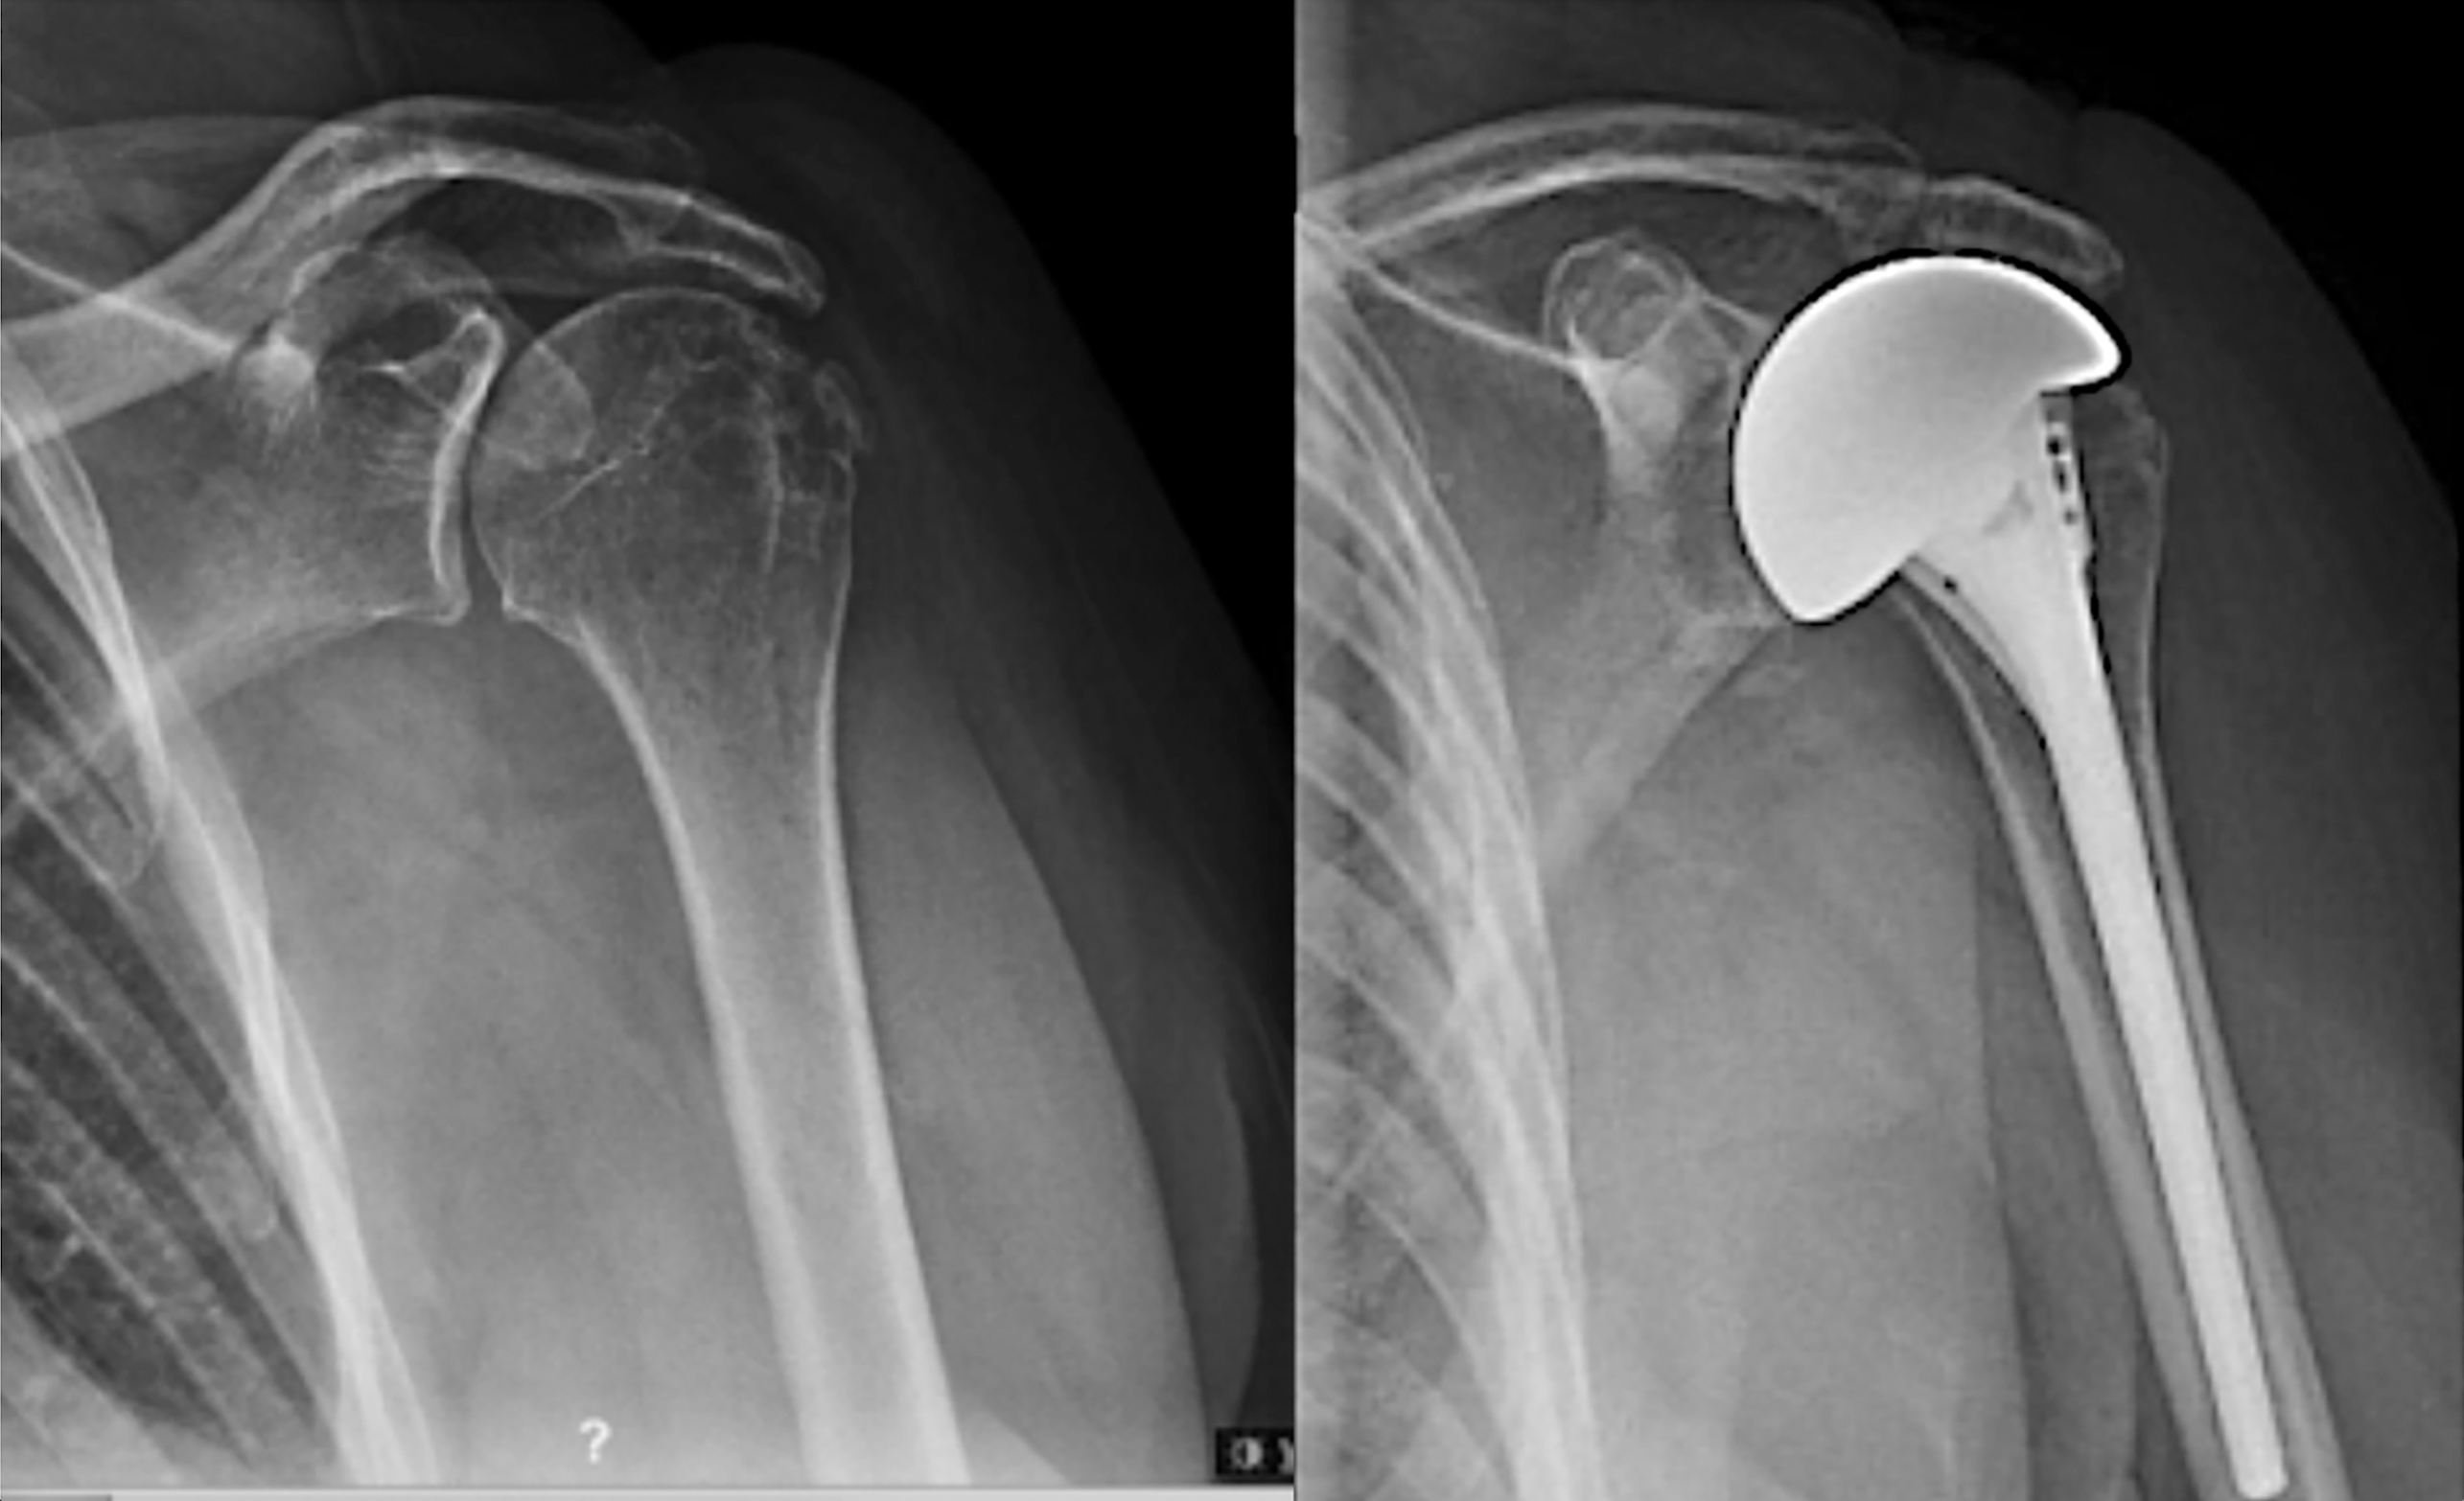

Case 3: X-rays shown below for an active muscular man in his early 60’s presented with a painful right shoulder after several failed attempts a rotator cuff repair. He had a stable shoulder and retained active elevation despite having irreparable subscapularis, supraspinatus, and infraspinatus tendon tears.

At one year after surgery, he returned with a comfortable shoulder with full active motion and progressively improving strength. Despite his subscapularis deficiency, he reported no problems with instability.

Case 4: An active man in his 70’s presented with pain and loss of function in his right shoulder. Despite having irreparable supraspinatus and infraspinatus tears and a torn subscapularis, he had active elevation above 90 degrees. At surgery his subscapularis was reconstructable. His preoperative and postoperative x-rays are shown here.

At three years after surgery, he returned for routine follow-up with a comfortable functional shoulder.